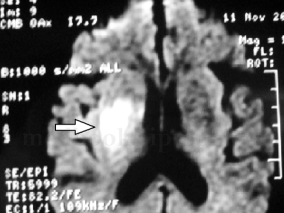

1小时条评论女,14岁,右利手。 主诉:突发右侧肢体偏瘫1年。 病史:1年前因突发右侧肢体活动障碍被外院诊断为脑梗死,在发病前没有外伤史、感染史(发热、上呼吸道感染、肠道感染),发病时无明显头痛。经保守治疗,保留右侧偏瘫后遗症至今。此后辗转于全国各大医院诊治查找...